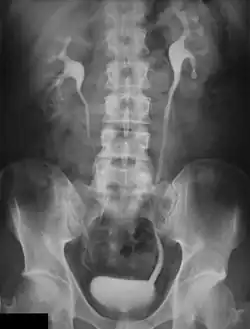

Urografie oder Urographie (altgriechisch οὖρον ouron „Urin“ und -graphie), synonym Pyelographie (altgriechisch πύελος pyelos „Wanne, Trog“, hier: „[Nieren-]Becken“), sind radiologische Methoden zur Darstellung der ableitenden Harnwege (Nierenbecken, Harnleiter und Harnblase). Die erzeugten Aufnahmen werden Urogramm beziehungsweise Pyelogramm genannt.

Diese Verfahren dienen zur Darstellung von Morphologie und Funktion der Nieren und der ableitenden Harnwege sowie zur Feststellung von Abflussbehinderungen, etwa durch Harnsteine. Uratsteine (Harnsäuresteine) sind röntgennegative Steine, das heißt, sie lassen sich im Röntgenbild nicht direkt darstellen.

Bei der retrograden Urografie (auch retrograde Pyelografie genannt), entwickelt durch Friedrich Voelcker und Alexander von Lichtenberg, Heidelberg 1905,[1] und bei dem Miktionszystourethrogramm wird eine Kontrastmittellösung über einen Blasenkatheter in das Hohlsystem instilliert. Zur sogenannten intravenösen Urographie, auch Ausscheidungsurographie (erstbeschrieben durch Volkmann 1922) genannt, werden ca. 50 ml eines jodhaltigen Röntgenkontrastmittels in eine Armvene injiziert und die Ausscheidung wird in einer Serie von Röntgenaufnahmen von Bauch und Becken verfolgt. Je nach Grad der Abflussbehinderung dauert das zwischen 15 Minuten und 24 Stunden.